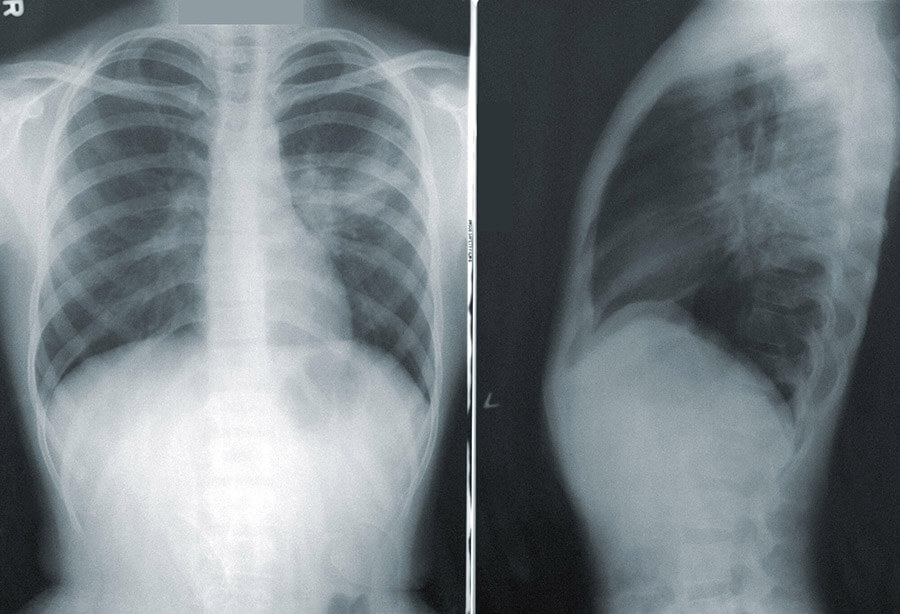

The doctor was exposed to the virus when the 38-year-old woman visited the clinic on March 12, the minister said. Five days later, she tested positive. That day, the doctor was also admitted in hospital.